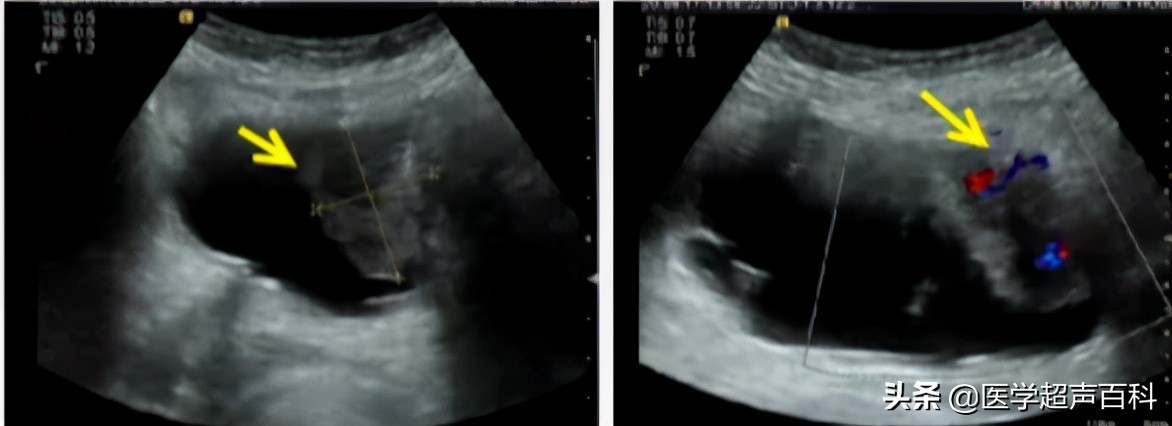

膀胱肿瘤的B超表现

膀胱壁可见菜花样、乳头状或团状中、强回声凸向膀胱,表面粗糙、不光滑,不随体位移动。

肿瘤多有瘤蒂与膀胱粘膜相连,连接处膀胱壁回声模糊,连续性中断,肿瘤基底部常较宽,膀胱壁局限性增厚。

CDFI:显示肿瘤基底部有细条状血流,多普勒频谱显示动脉频谱:RI〉0.60。